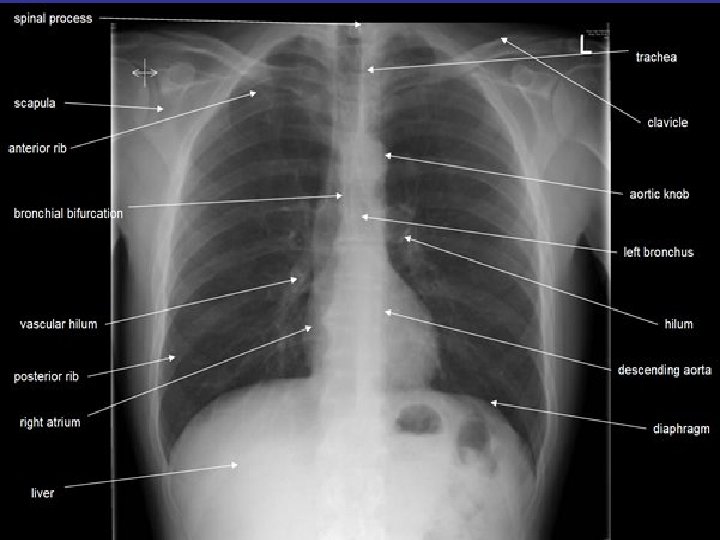

How to read a chest x ray ? • 1 - chest wall, bones

How to read a chest x ray ? • 1 - chest wall, bones and abdomen * bones; lesions or fractures * soft tissue ; mastectomy or soft tissue tumors • 2 - heart and mediastinum * trachea ; position & caliber * hila : lymphadenopathy * mediastinum contour : ? mass * heart : cardiac configuration • 3 - lungs opacity or lucency